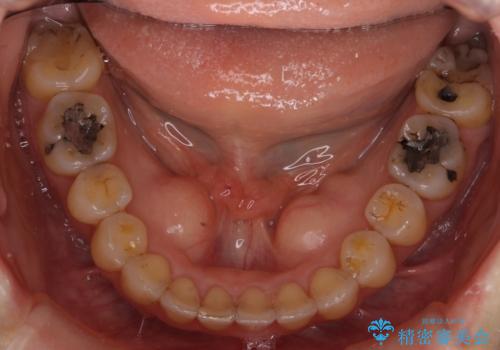

結果、非常に真面目に治療に取り組んでいただき、期間はかかりましたが予想以上の結果を得ることができました。

マウスピース矯正の治療には患者様のご協力が不可欠で、治療の成否を分けると言っても過言ではありません。